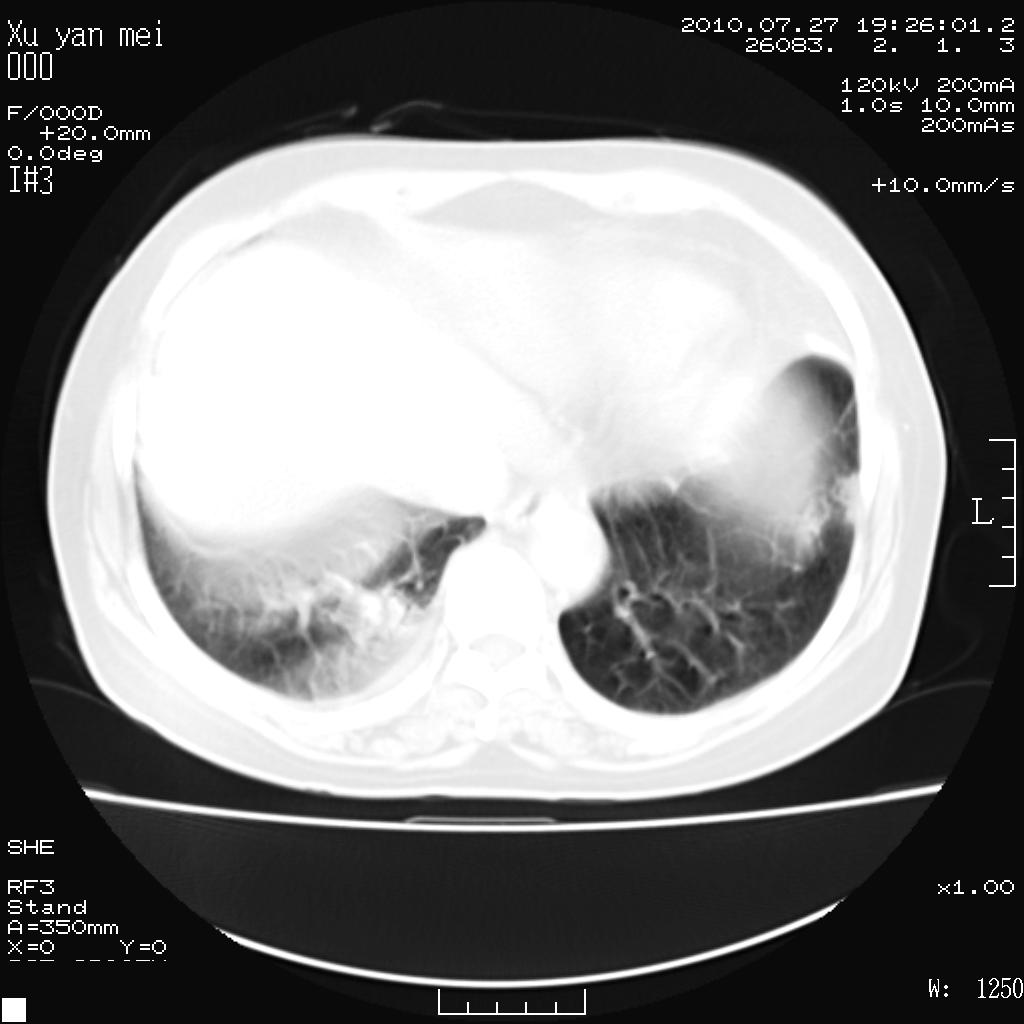

女,60岁,胸痛就诊,右肺结核?炎症?其它?(胸片右侧中上肺野确实看不到什么啊)

1)考虑两肺感染性病变;建议抗炎治疗后复查。2)双侧少量胸腔积液。

1)考虑两肺感染性病变;建议抗炎治疗后复查。2)右侧少量胸腔积液。

双肺炎症可能性大,建议抗炎后复查。右侧胸腔少量积液。双侧胸膜轻度增厚。

考虑两肺感染性病变;不除外肺栓;建议抗炎治疗后复查。